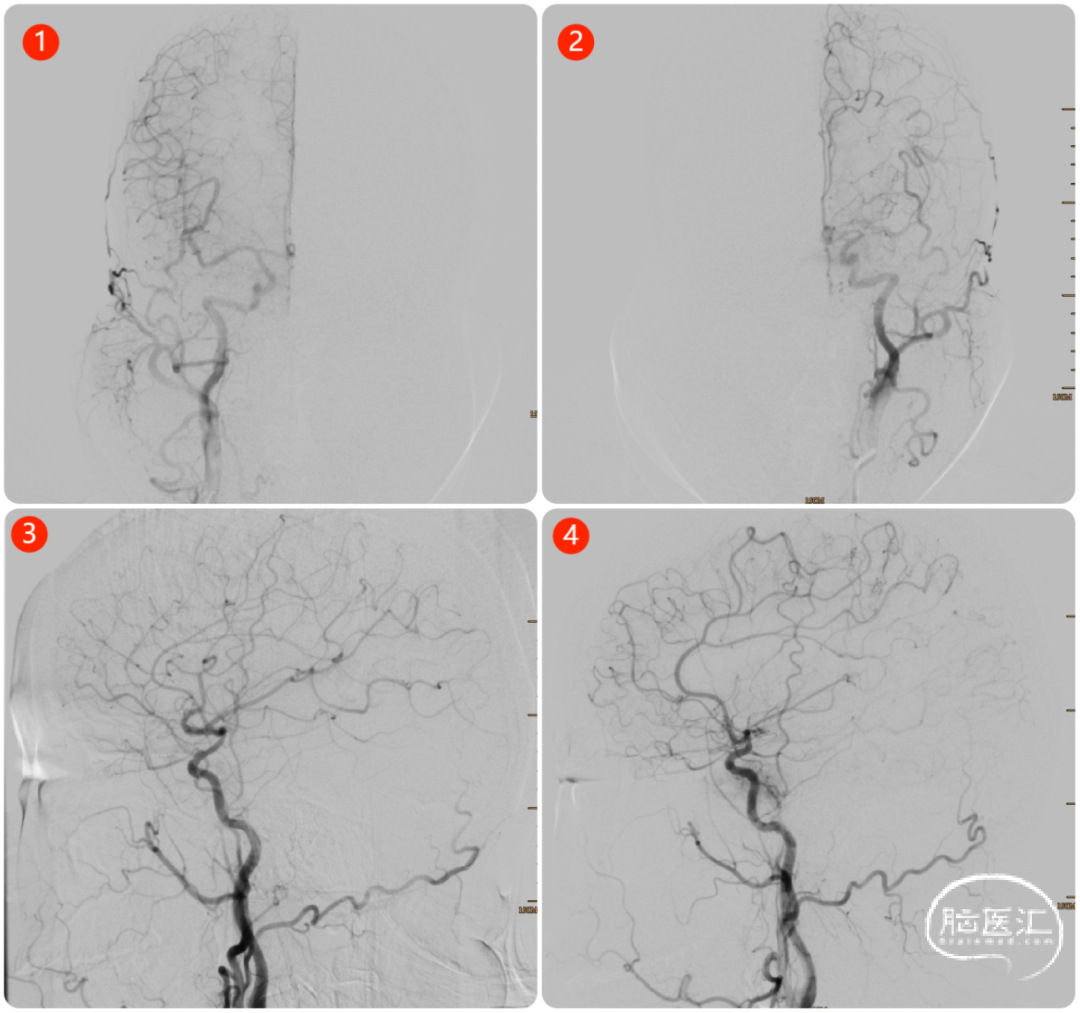

脑血管造影检查:术中见右侧颈内动脉眼动脉段以远变细,左侧大脑中动脉M1段消失,烟雾样血管增生(图3、4)。后循环无明显向前代偿。

图3. ①③右侧颈总动脉造影;②④左侧颈总动脉造影